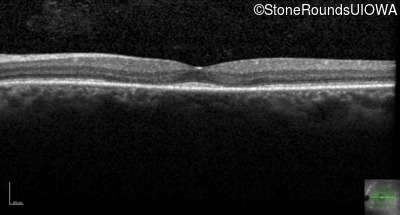

This 44 year old man became photophobic about 6 years ago. He has been taking Imuran since his kidney transplant 23 years ago.

| Age at visit: 46 years |

| Senior-Loken Syndrome | NPHP1 | Gly343Arg G(GG)>A(GG) | Deletion of Entire Gene | AR |